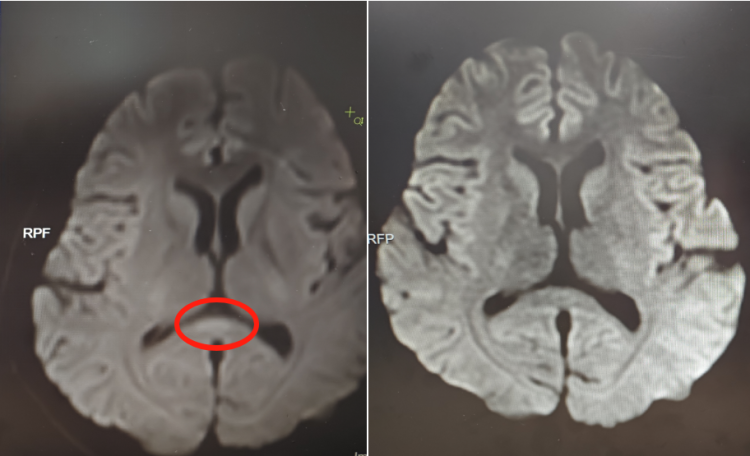

该院神经内六科医生接诊后,初步判断为脑炎。完善血清、脑脊液检测等,结果不支持颅内感染及自身免疫性脑炎,进一步完善细胞因子等炎症指标,结合核磁共振等,最终诊断阿婷为副感染性脑病。

▲治疗前(左)核磁共振提示胼胝体压部病变

好在接受相应治疗后,阿婷的意识逐渐恢复,情绪日趋稳定,已于近日康复出院。